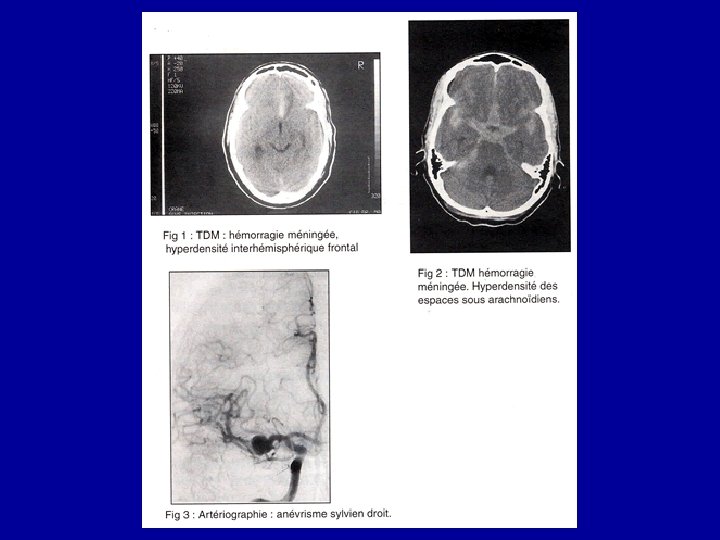

• Le Scanner cérébral en urgence • Présence de sang dans les citernes arachnoïdiennes de la base ou dans le parenchyme ou dans les ventricules. • Détecte un hématome intracérébral, une hydrocéphalie aigue

• Artériographie cérébrale • Explore les 4 axes (2 carotides, 2 vertèbrales) • Démontrer l'existence d’un anévrysme • Localisation • Mode d’implantation • Nombre